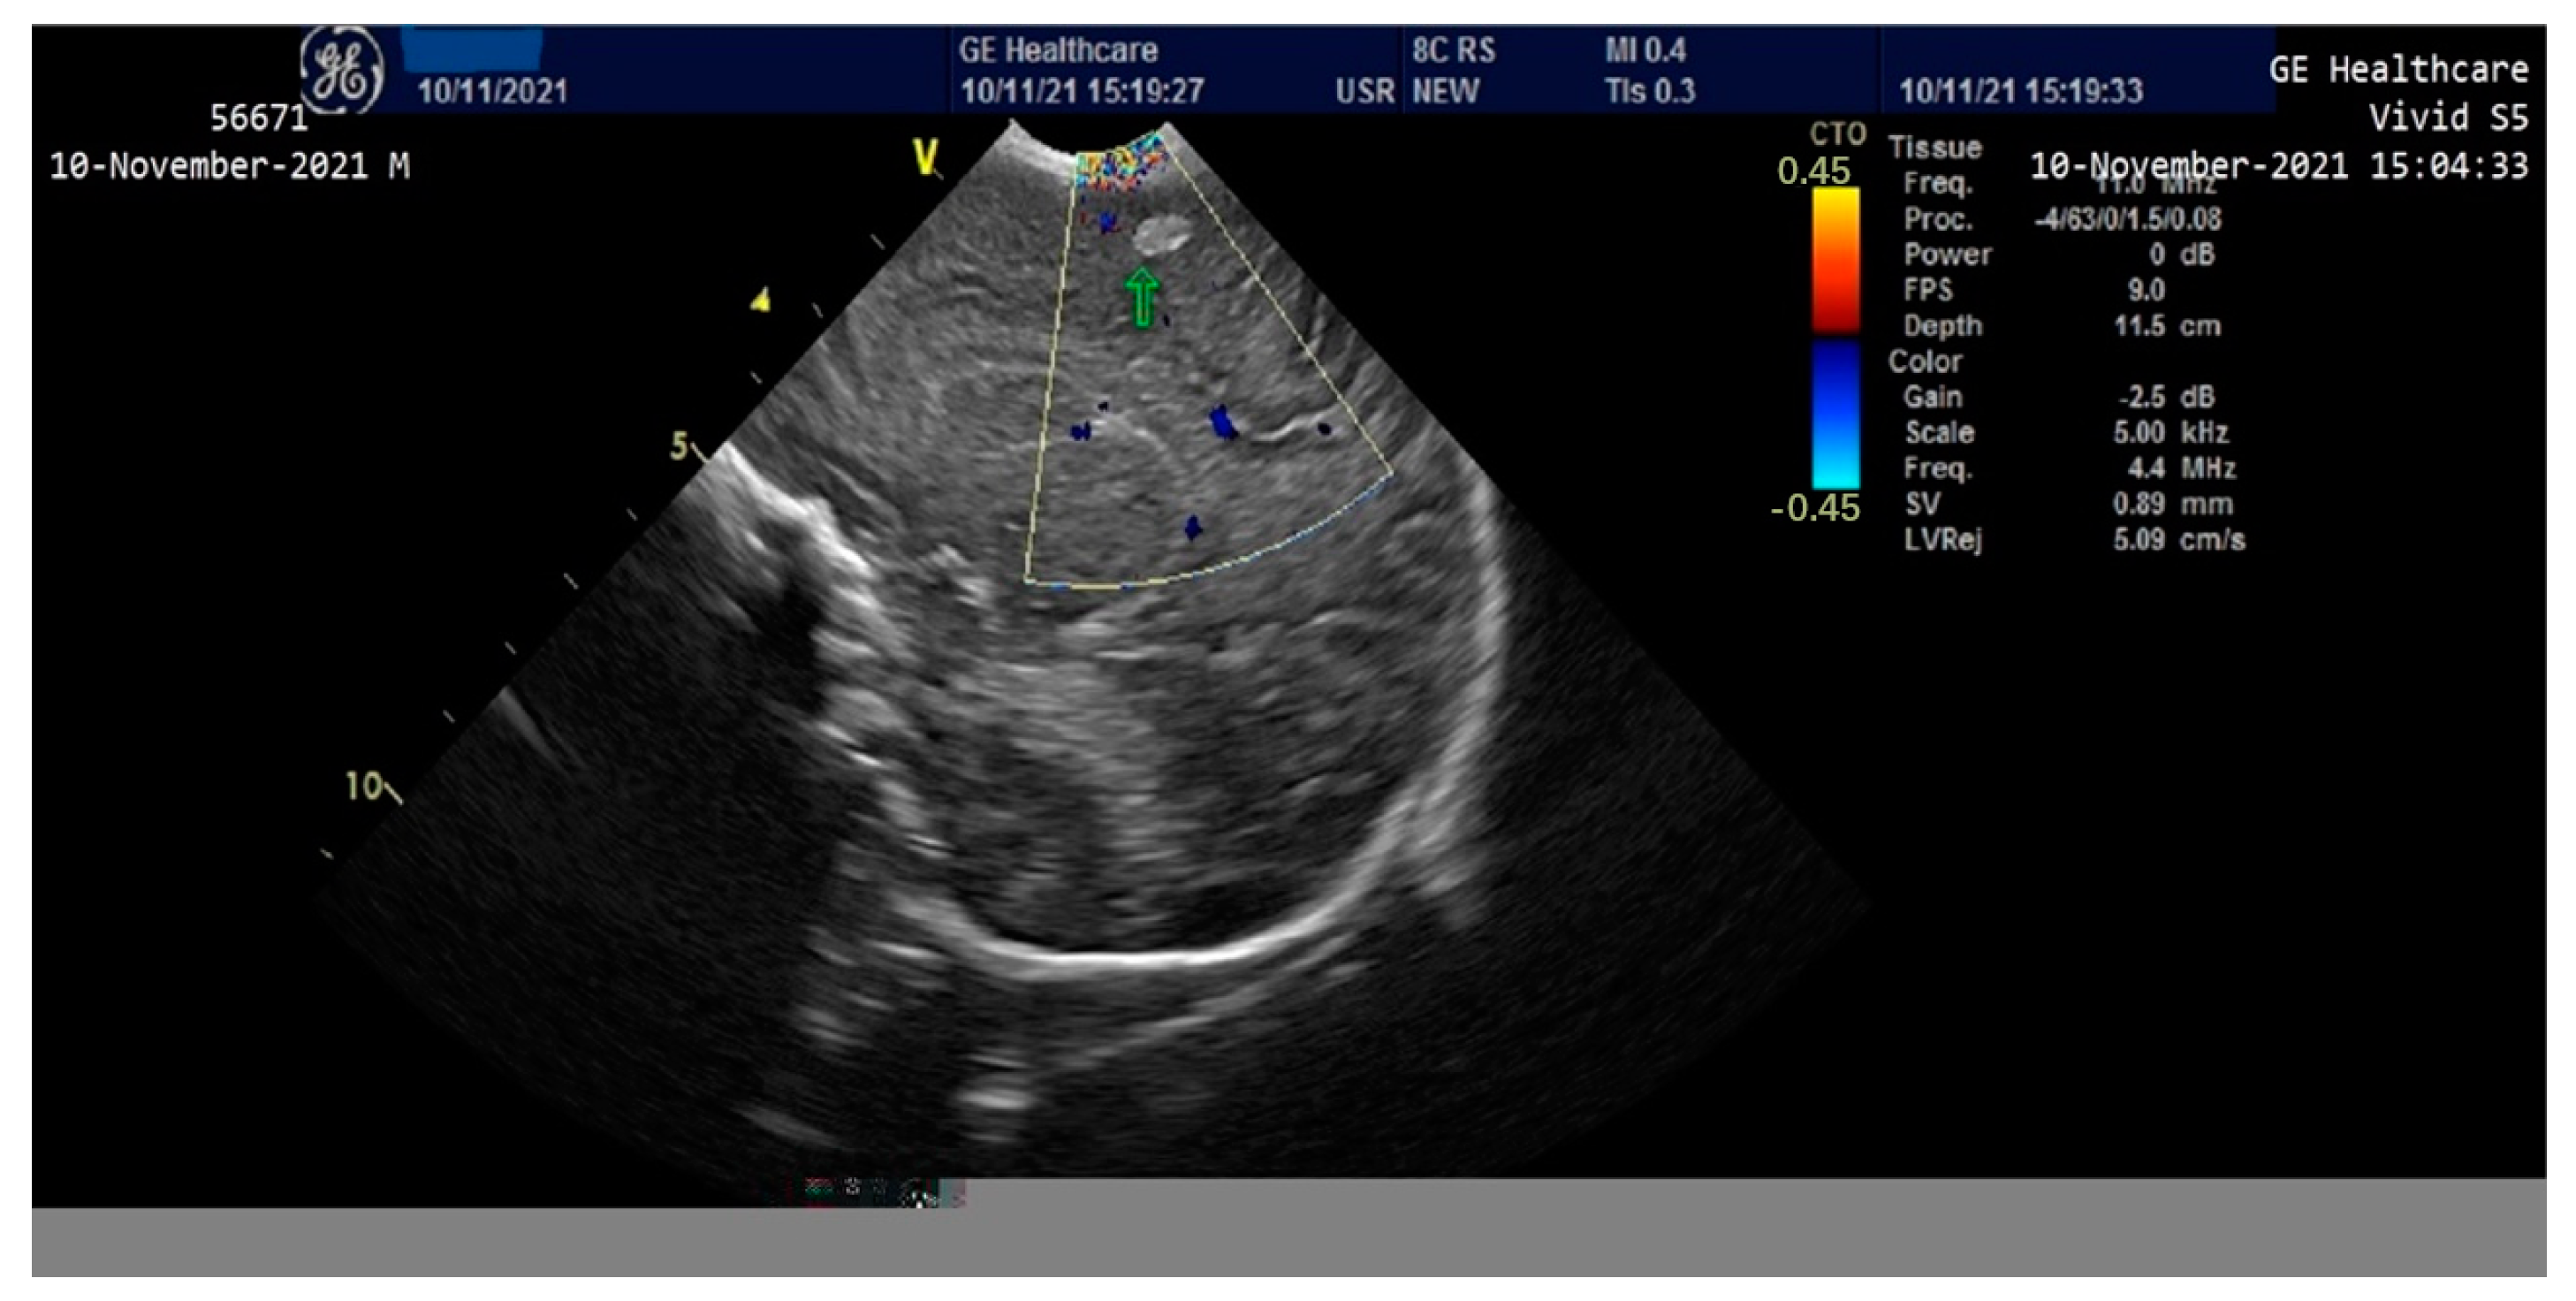

On the third day of life, the patient presented clinically and electrically generalized tonic-clonic seizures (aEEG monitoring)—requiring administration of Phenytoin (i.v) and Midazolam until the 8th day, then continued with Phenobarbital per os. A cranial ultrasound performed on the second day of life showed a round-oval hyperechoic image of 0.6/0.4 cm in the relatively superficial left frontal-parietal cerebral parenchyma which evolved to a left periventricular leukomalacia and left porencephalic cyst at one month of age (Figure 3 and Figure 4). The edema gradually reduced and the ascites disappeared; the intestinal transit became functional after 3–4 days and the enteral feeding was initiated. Parenteral nutrition was discontinued after 14 days. Neurological examination at one month of age accompanied by an EEG recording did not show any significant abnormalities. The patient was discharged after 40 days of hospitalization. At 2 months of evaluation, the patient showed an ascending weight curve and significant improvement in cytolysis and hepatic cholestasis.

Figure 3.

Cranial ultrasound in the first 24 h of life with round-oval hyperechoic image 0.6/0.4 cm in the left frontoparietal cerebral parenchyma.